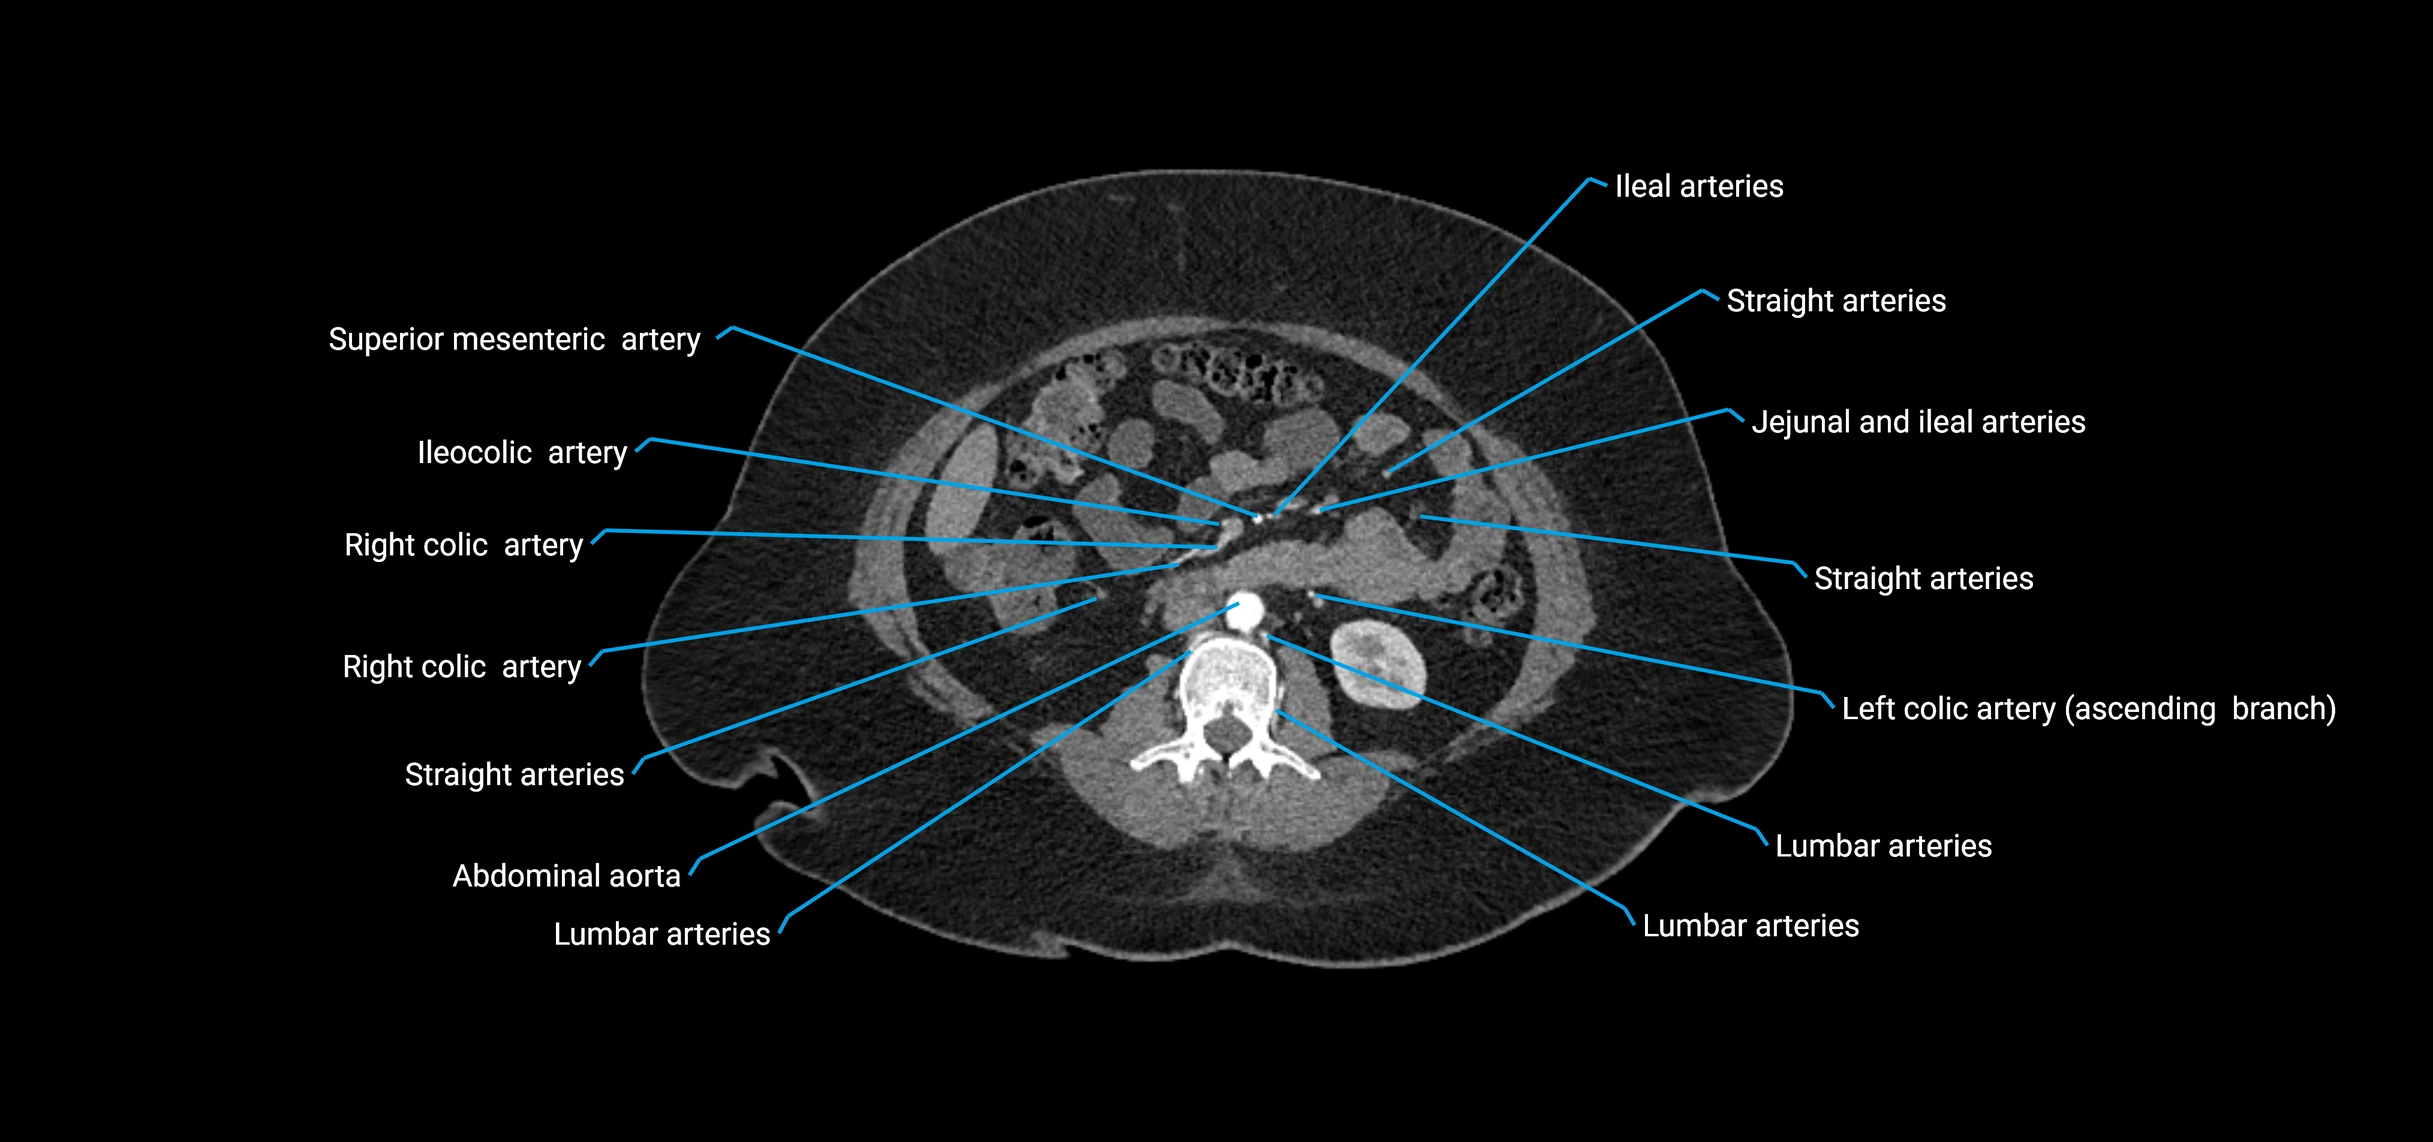

CT images

image

Contrast-enhanced CT (CTA):

• Gold standard for abdominal aortic imaging

• Provides excellent detail of lumen, wall, aneurysm, thrombus, and branch vessels

• Multiplanar and 3D reconstructions help in aneurysm measurement, stent graft planning, and dissection evaluation